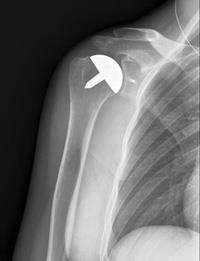

Resurfacing hemiarthroplasty

This X-ray shows the cap-like prosthesis used in resurfacing hemiarthroplasty.